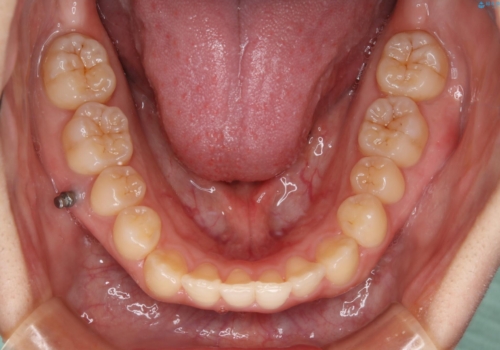

八重歯とクロスバイト:インビザライン治療

- 八重歯が気になるとの事でご相談にいらした方です。

インビザラインで綺麗に並べました。

気になっていた八重歯が綺麗になって大変喜んでいただけました。